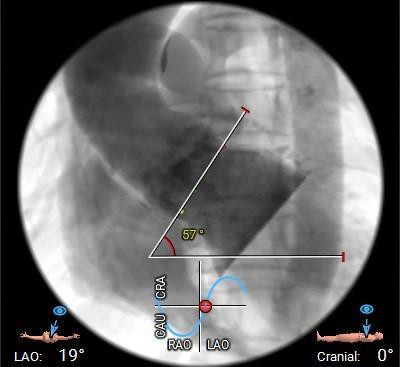

主动脉瓣水平夹角约57°,非横位心,主动脉弓宽度角度可;